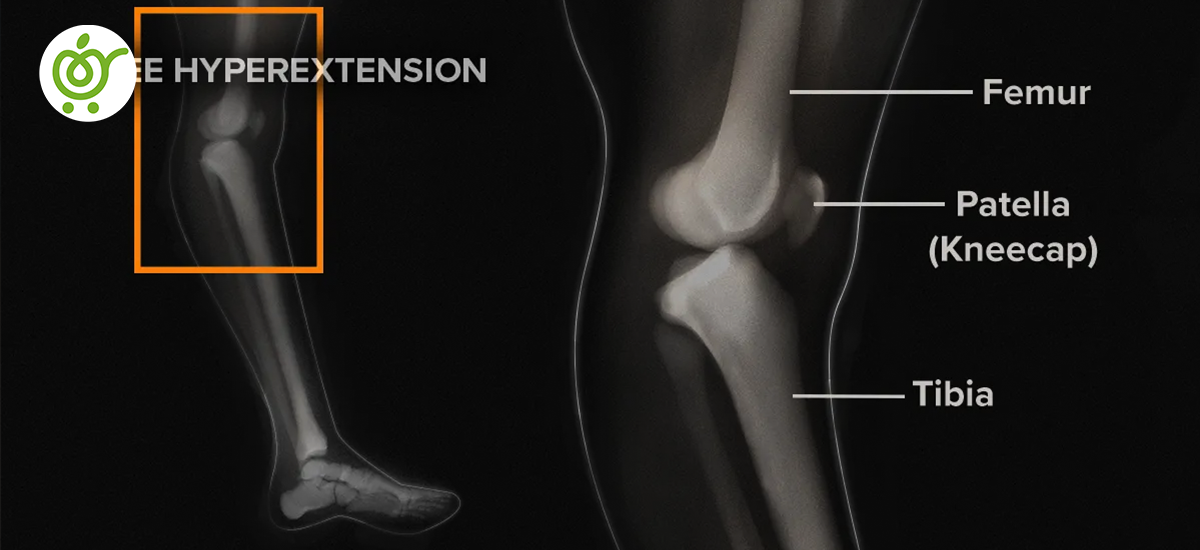

عقبزدگی زانو، که به عنوان هایپر اکستنشن زانو یا ژنو رکورواتوم (Genu Recurvatum) نیز شناخته میشود، نوعی ناهنجاری در مفصل زانو است که باعث خم شدن غیرطبیعی زانو به سمت عقب میشود. در این حالت، وقتی فرد ایستاده است، استخوان ساق پا نسبت به استخوان ران بهطور غیرعادی عقبتر قرار میگیرد. این ناهنجاری موجب میشود که مفصل تیبیو فمورال (محل اتصال استخوان ران به درشتنی) بیش از حد مجاز که به طور طبیعی بین ۰ تا ۱۳۵ درجه است، باز شود.

تشخیص عقبزدگی زانو معمولاً با استفاده از معاینه فیزیکی و تصویربرداری انجام میشود. پزشک ابتدا طرز راهرفتن بیمار و میزان محدودیت حرکت زانو را بررسی کرده و از او درباره علائم و نشانهها سؤال خواهد کرد. یکی از روشهای ابتدایی برای ارزیابی شدت عقبزدگی زانو، اندازهگیری ارتفاع پاشنه پا است. در صورتی که فقط یکی از زانوها تحت تأثیر قرار گرفته باشد، با مقایسه ارتفاع پاشنه پای درگیر و پای سالم میتوان شدت عقبزدگی را تعیین کرد.

برای تشخیص دقیقتر و بررسی آسیبهای احتمالی، ممکن است پزشک درخواست تصویربرداریهای خاصی کند، از جمله:

- تصویربرداری با اشعه ایکس

- امآرآی (MRI)

- سیتیاسکن (CT)

این تصویربرداریها به پزشک کمک میکنند تا آسیبهای داخل و اطراف زانو را مشاهده کرده و مشخص کنند که آیا مشکلات جدیتری مانند پارگی رباط وجود دارد یا خیر.